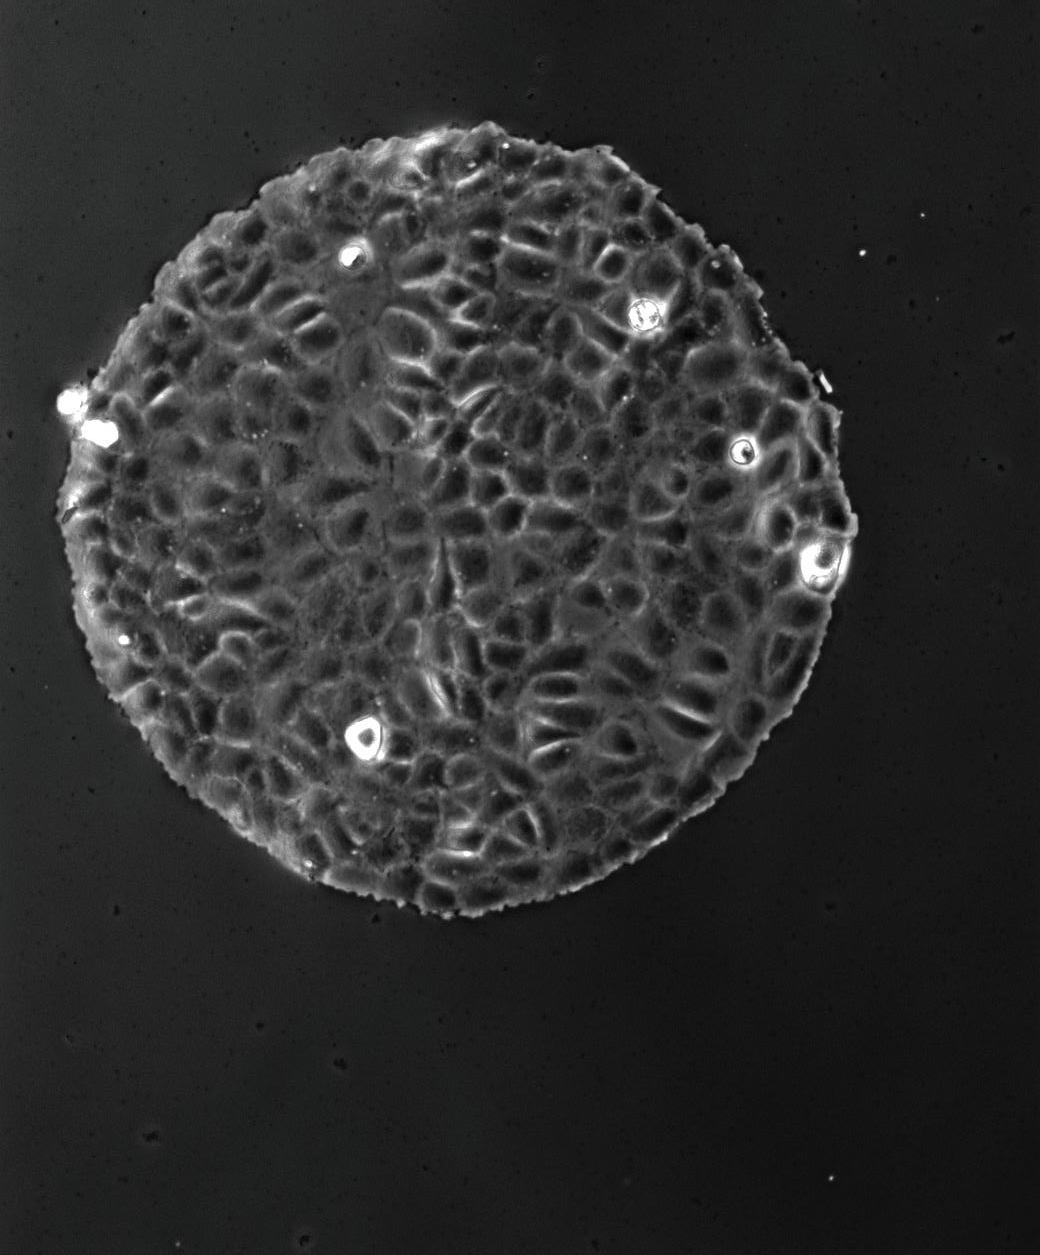

A pesar de que las terapias contra el cáncer han evolucionado, aún queda el desafío de lograr tratamientos más efectivos. El principal problema de las terapias tradicionales es su toxicidad y el desarrollo de resistencia por parte de las células tumorales. Contamos con un gran número de terapias dirigidas, sin embargo, en muchos casos, las mismas apuntan contra lo que se denomina el “bulto” tumoral, sin eliminar a una pequeña población de células denominadas “madre” o iniciadoras de tumor. Estas son las responsables del desarrollo de metástasis y recurrencias. En este contexto, la nanotecnología se presenta como una herramienta prometedora para delinear nuevas estrategias terapéuticas, ya que permite, por sus características, dirigirse a varios blancos en simultáneo. En el área de nanomedicina del INS trabajamos de manera interdisciplinaria en el diseño de nanopartículas multifuncionales basados en dos ejes: 1) expertise en el diseño y síntesis de nanopartículas multifuncionales; 2) sólidos conocimientos de los mecanismos implicados en la progresión tumoral. El objetivo final de este equipo de trabajo es el desarrollo de terapias que se dirijan exclusivamente al tumor, disminuyendo la toxicidad sistémica, y que eliminen a las células responsables de la recurrencia tumoral.

Although cancer therapies have evolved in the last 50 years, still today, as researchers, we face the challenge of achieving more effective treatments for this family of diseases. The main problem of traditional therapies is their toxicity and the development of resistance. Even though most therapies are targeted to specific tumor cell pathways, many are effective against the tumor bulk, but do not eliminate infiltrating immune cells or cancer stem cells that are key players in progression and recurrence. In this context, nanotechnology is a promising tool to delineate new therapeutic strategies, since it allows to tackle several targets simultaneously. In the Nanobiology laboratory of the INS we work interdisciplinary in the design of multifunctional nanoparticles based on two axes: 1) expertise in the design and synthesis of multifunctional nanoparticles; 2) solid knowledge of the mechanisms involved in tumor progression. The goal of this team is the development of therapies that target different key players within the tumor, decreasing systemic toxicity, and eliminating the cells responsible for tumor progression and recurrence.